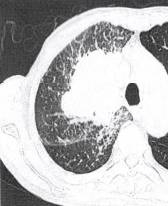

(1)周围型肺癌基本X线表现为肺内孤立的球形灶,不同组织类型的肺癌在大小、 医学百科网 | YxBaike.Com

密度、边缘形态及瘤体周围特点有一定差异。CT的优势在于可显示瘤体内密度、坏死、血供特点及临近结构浸润情况。除边缘凹凸不平,呈分叶征外,常可见边缘毛刺、瘤周血管集束征、胸膜凹陷征、内部空洞形成,多壁厚薄不均,内缘凹凸不平或见壁结节。无或少有气液平为其特征(图2)。增强检查病灶可见明显强化,CT值增加25Hu以上。高度提示 肺癌。 医学百科网 | YxBaike.Com